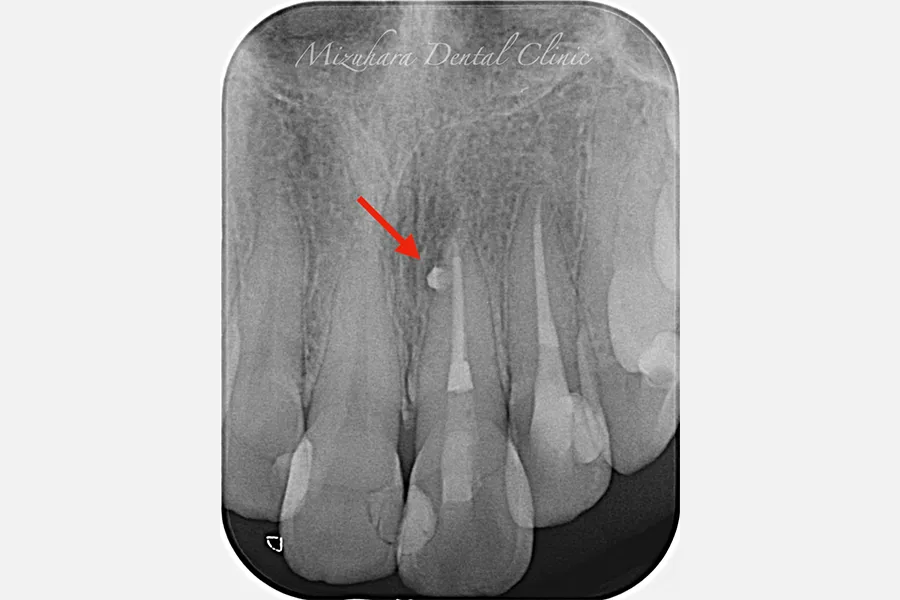

予知性の高い治療を提供できるだけ患者様の大切な歯を残し、10年、20年先まで健康な状態を保てるよう、長期的な視点で治療を計画します。そのために最も重要なのが、「診査」と「診断」です。的確な診断は精密な診査から生まれ、治療結果を大きく左右します。問診や簡易検査だけでは見逃されがちな病変も、CTやマイクロスコープなどの最新の医療機器を活用し、時間をかけて丁寧に「診査・診断」を行います。

世界基準の成功率を目指した精密根管治療

当院では豊マイクロスコープ、ラバーダムを使用し、世界基準の成功率を目指した精密根管治療による「歯を残す」ための治療をご提供します。